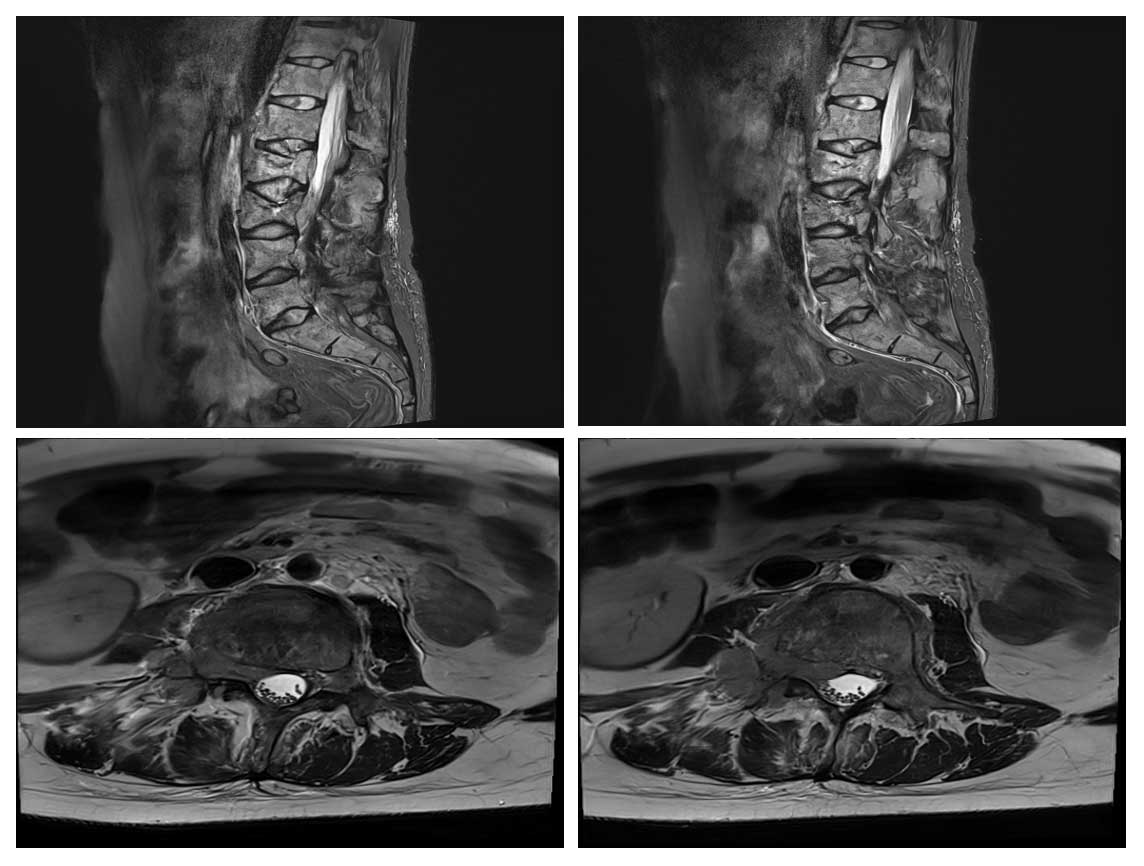

Ameliyat Öncesi: MR’da iki seviyede patolojik kırık, epidural ve kök basısı görülmekte.